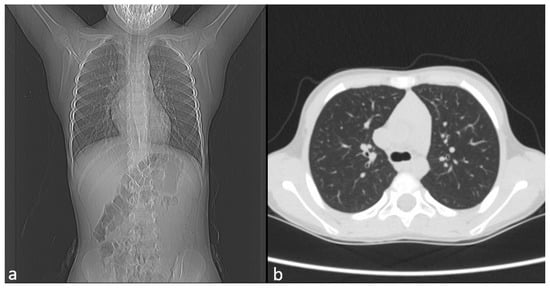

Chest CT showed no pulmonary pathology or structural vascular anomalies, as shown in Figure 2a,b, whereas abdominal ultrasound and echocardiography also revealed no abnormalities.

Figure 2. Image of CT. (a) Frontal view. (b) Axial view.